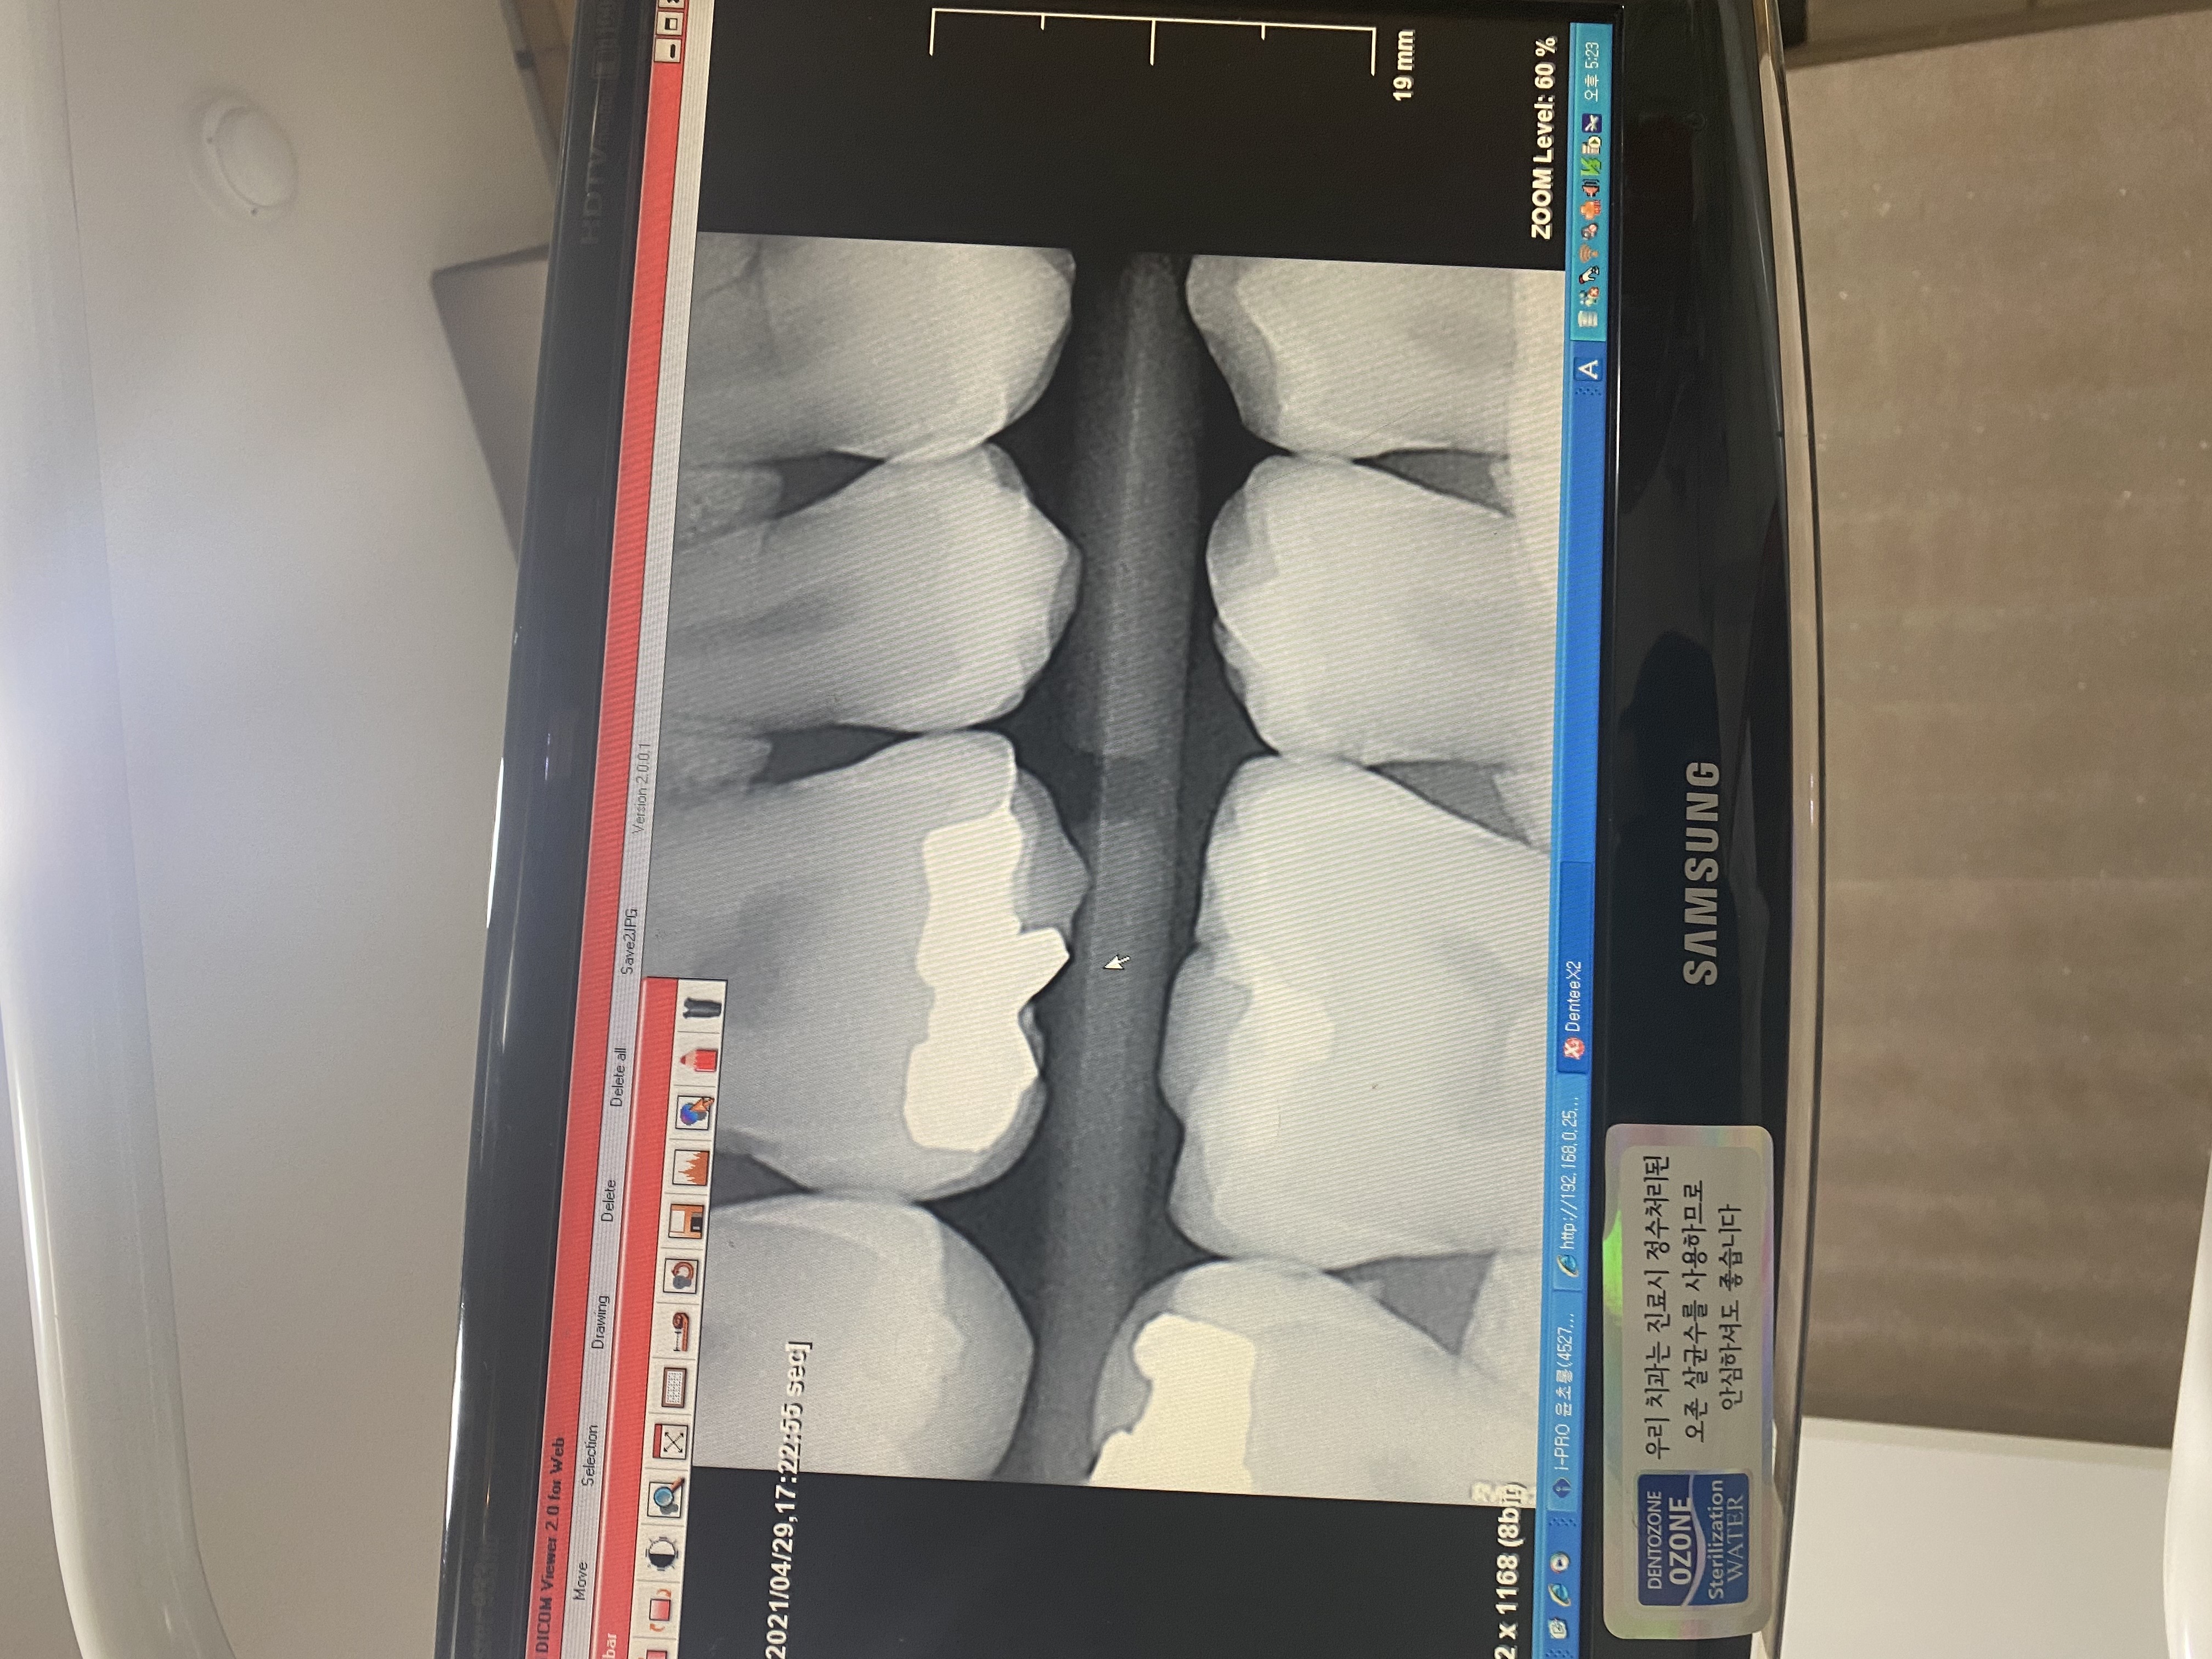

안녕하세요 선생님. 몇해전 선생님 조언으로 많은 도움을 받았었습니다. 이번에 가족이 통증이 있어 치과에 방문했는데 신경치료 또는 임플란트를 추천하더라고요. 제가보기에는 문제의 치아보면 치아부분에는 검게변하지 않아서 충치가 안보이는거 같은데 병원에서는 신경치료나 임플란트를 권하네요. 뿌리끝에도 검은 부분이 없는거 같고요. 뿌리사이에는 검게 염증이 보이는거 같습니다. 사진상으로 정확한 진단은 힘드시겠지만 조언좀 부탁드립니다. 2년전 선생님 말씀대로 신경치로안받고 저도 별다른 통증없이 잘 관리하면서 치아를 사용하고 있어서 항상 감사드립니다.

• 작성자hyuntae 작성자 본인 여부 작성자 | 작성시간 21.05.01 선생님 조언 감사드립니다. 염증이 심한건가요? 보통 검게 나오는게 염증으로 알고 있는데 사진상으로는 뿌리끝은 하얀거 같고 뿌리 사이가 검은거 같은데 그쪽이 염증이 심한건가요?